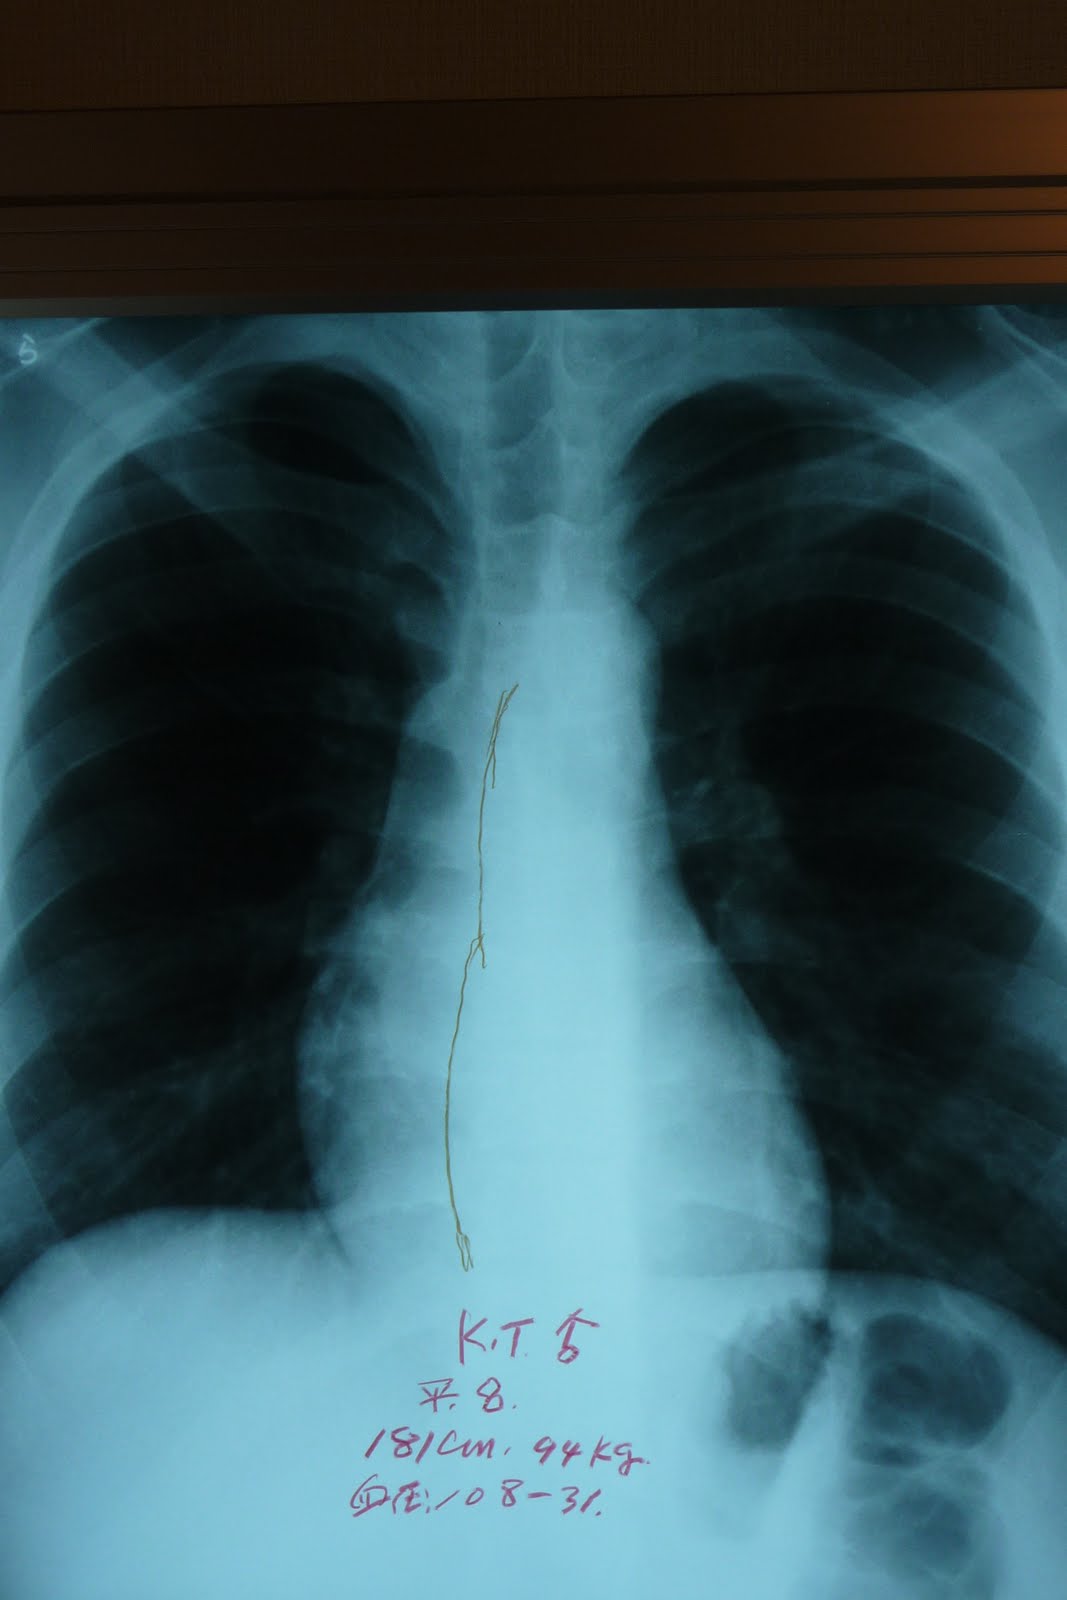

(線が正しい大きさです)

医学的(検査的)には、肺動脈第二音の亢進、最低血圧の下降、胸部レントゲンで心臓陰影の右方拡大(心臓肥大)、筋肉の圧痛など。

これを教えてあげた60歳の主婦の人が、四か月で心臓の肥大が縮小した(体も軽くなり、肩こりも良くなった)例もあります。なにか感じられた”方は、お試しになってみてください。